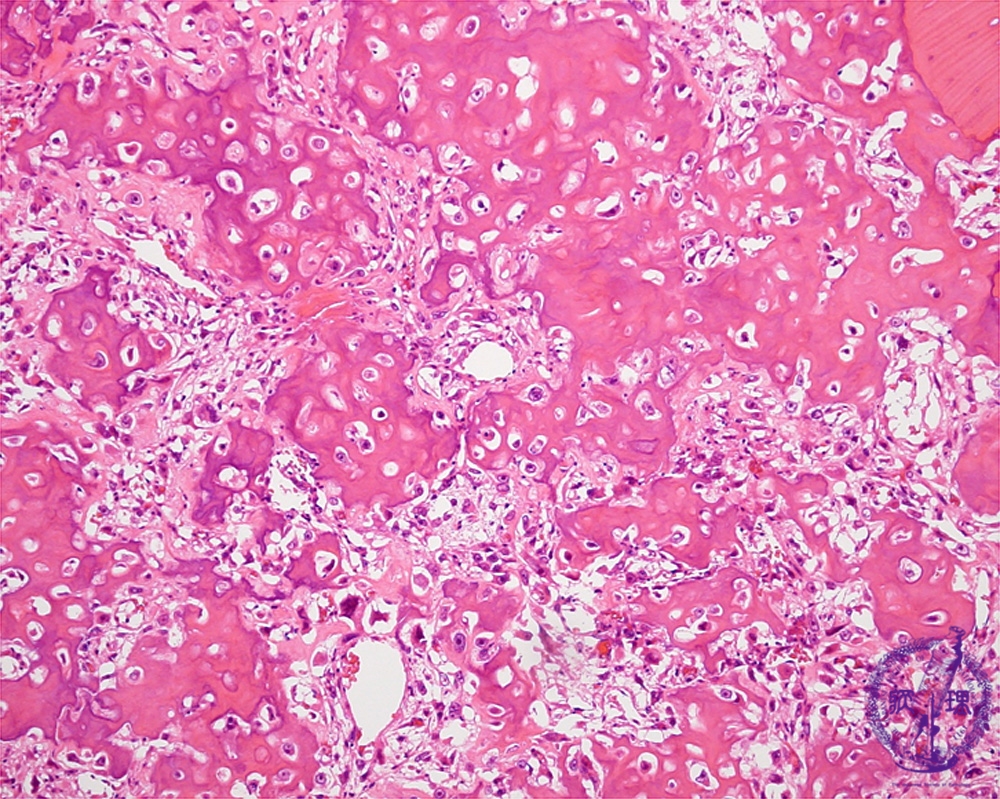

Microscopic view (HE; middle power view): Tumor cells with abundant hyperchromatic nuclei form eosinophilic amorphous osteoid.